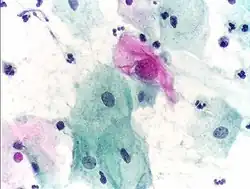

Micrograph of a Pap test showing trichomoniasis. Trichomonas organism seen in the upper right. Pap stain.

Infestation by Trichomonas vaginalis